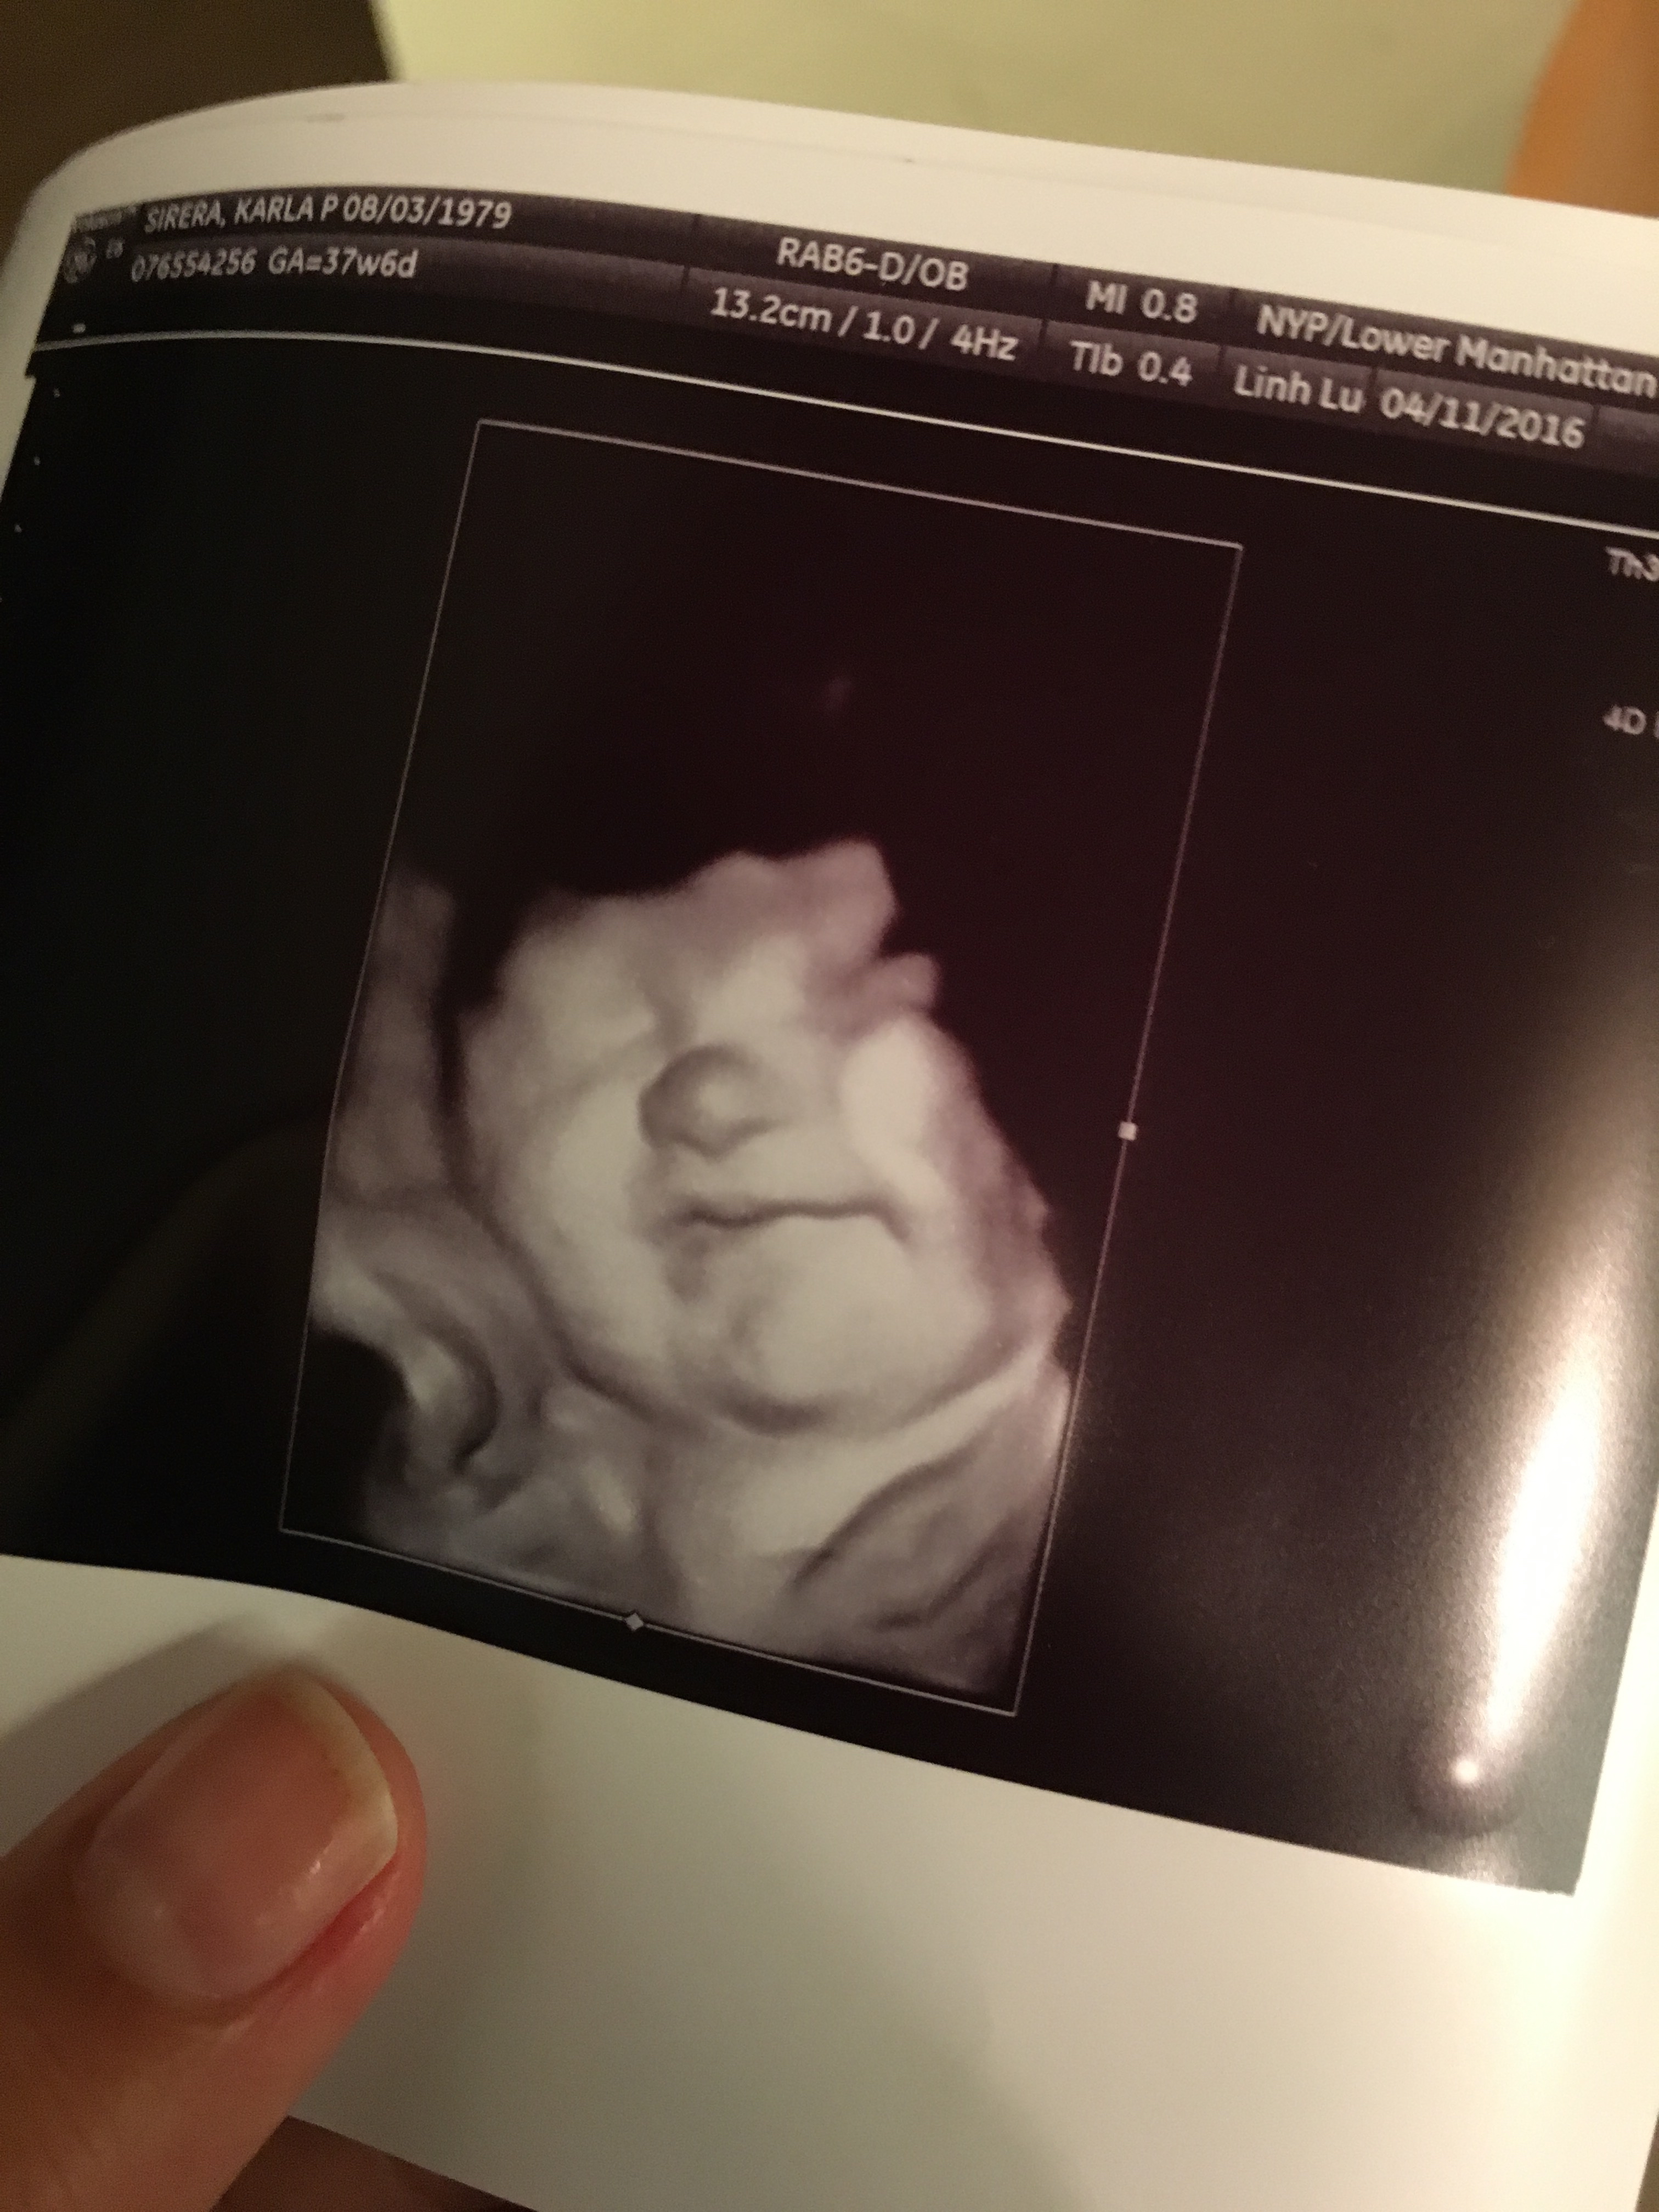

A week before our little one arrived 🙂 All you see in this picture is a pair of cheeks and a button nose, and thats exactly what everyone noticed when she was born.